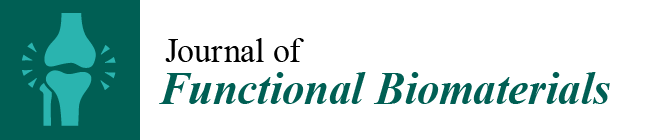

3.1. Esthetic Criteria

3.2. Biological Criteria